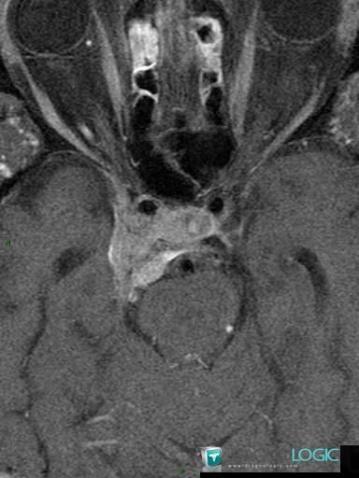

- Diagnosis Meningioma, Location(s) Pituitary gland and parasellar region, with gamuts Cavernous sinus lesion, Sellar and parasellar mass